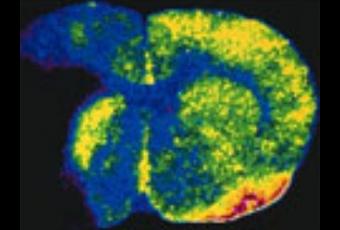

Source: Nature Genetics(2012)doi:10.1038/ng.1081 Published online 05 February 2012 Genome-wide association study identifies a variant in HDAC9 associated with large vessel ischemic stroke(Visuel Welcome Trust: Topographie de l'ischémie cérébrale après l'obstruction d'une artère cérébrale. Les couleurs représentent le flux sanguin du débit le plus élevé au plus faible avec les couleurs blanche, rouge, jaune, vert, bleu et noir. Crédit: Dr I M Macrae)